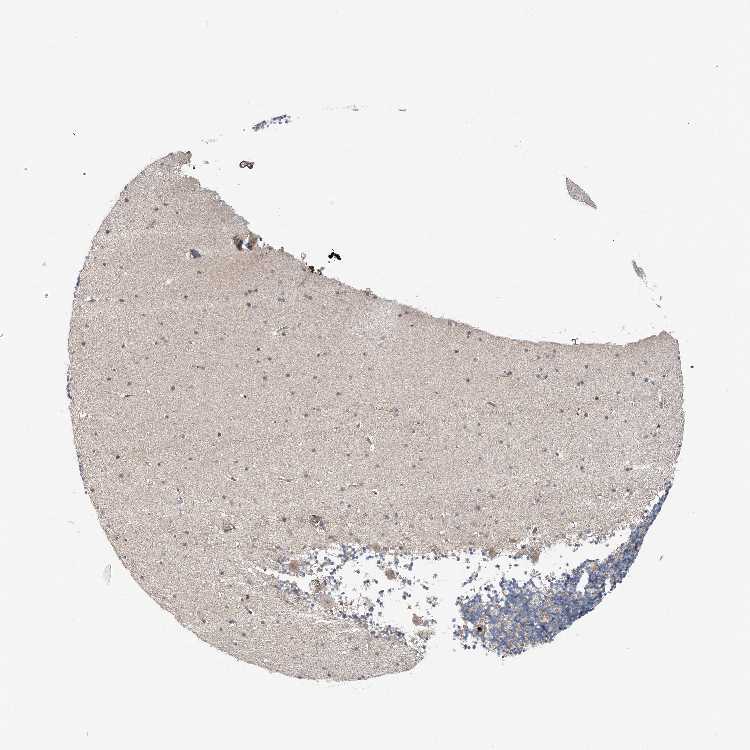

CEREBELLUM - Antibody stainingi

Antibody staining in the annotated cell types in the current human tissue is reported as not detected, low, medium, or high, based on conventional immunohistochemistry profiling in selected tissues. This score is based on the combination of the staining intensity and fraction of stained cells.

Each image is clickable and will lead to virtual microscopy that enables deeper exploration of all samples and also displays staining intensity scores, fraction scores and subcellular localization as well as patient and tissue information for each sample.

Antibody CAB034230

Purkinje cells Not detected

Cells in granular layer Not detected

Cells in molecular layer Not detected